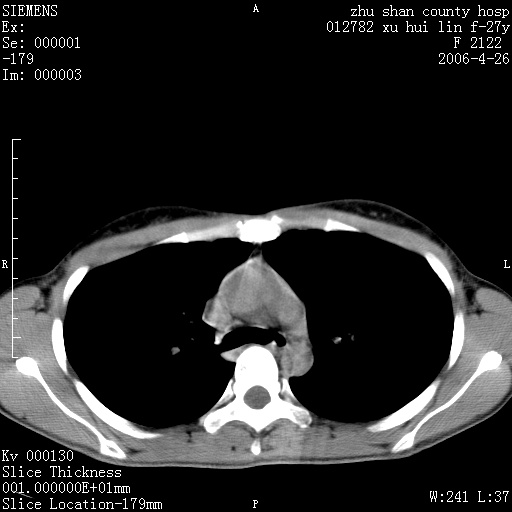

女性 病人 27岁!本院职工家属,五月前因感冒透视发现病变,ct示:左肺下叶背段感染性病变。经过半月规范抗生素治疗后复查病变无明显变化,后行四月规范抗痨治疗,复查无明显变化,后复查无效!请大家帮忙看看!

右肺下叶背段见片状高密度区,边界不清,密度不均,无钙化及空洞影,背段支气管通畅。所见层面肺门及纵隔内未见明显肿大淋巴结影。

女性 病人 27岁!本院职工家属,五月前因感冒透视发现病变,ct示:左肺下叶背段感染性病变。经过半月规范抗生素治疗后复查病变无明显变化,后行四月规范抗痨治疗,复查无明显变化,后复查无效!

诊断:首先还是考虑为慢性炎症。

从战友提供的ct图象及定位图象看应该是间质性炎症改变.如果患者不放心可建议她行纤支镜检查.